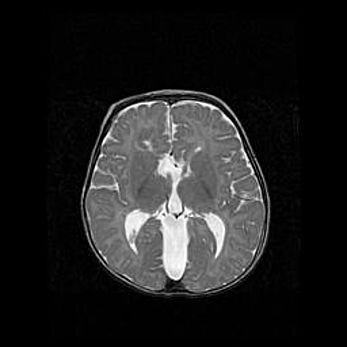

Сообщающаяся гидроцефалия. Кистозная энцефаломаляция головного мозга.

Возраст: 3 месяца 4 дня

Вес: 3100 г

Пол: женский

Окружность головы: 34 см

Срок гестации: 31 неделя

Кистозная энцефаломаляция головного мозга - одна из форм поражения головного мозга в детском возрасте. Характеризуется возникновением множественных и распространённых кист в коре, белом веществе и подкорковых образованиях головного мозга у плодов, новорождённых и детей раннего возраста. Развитие кистозной энцефаломаляции связано с внутриутробной асфиксией и гипотонией, родовой травмой, тромбозом синусов, пороками развития сосудов, инфекциями, сепсисом и другими причинами. Наиболее значимые инфекционные агенты: вирусы простого герпеса, цитомегалии, краснухи, токсоплазмы, энтеробактерии, золотистый стафилококк и другие.